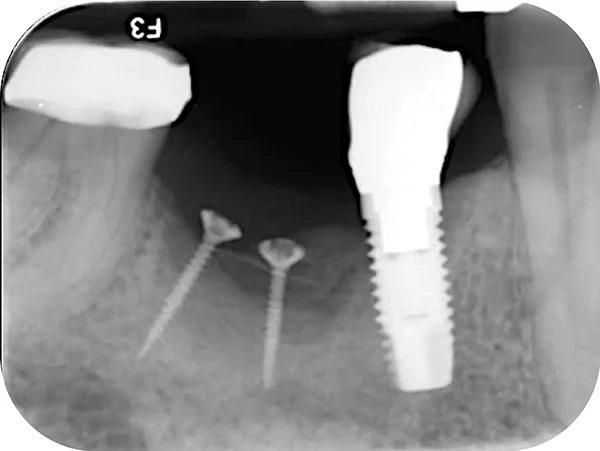

После процедуры НРК, установки имплантата и во время последующих заживление тканей прошло без осложнений. Рентгенологическое исследованиеспустя 24 недели после вмешательства (фото 12) потвердило процесс формирования новой костной ткани в вертикальной и горизонтальной плоскостях. В частности наложение изображений первоначального и послеоперационного снимков КЛКТ позволило установить вертикальное и горизонтальное увеличение кости от 7 мм до 9 мм по всей протяженности дефекта (фото 6 и фото 12). Через год после установки имплантата клинические и рентгенологические исследования показали сохранение достигнутой костной регенерации (фото 14).

Фото 14. Прицельный рентгеновский снимок выполнен 1 год спустя после проведенного оперативного вмешательства.